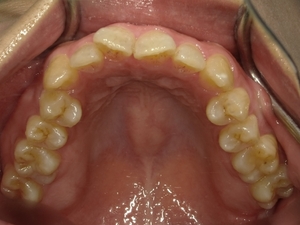

◯ご相談内容:歯並びが気になる◯矯正の種類:マウスピース型矯正「インビザラインGO」◯治療期間:20週間◯治療費用:44万円(税込)